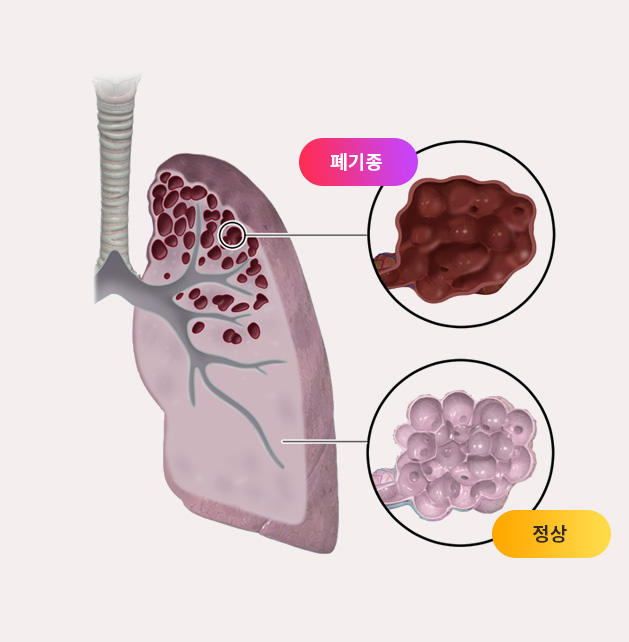

해외논문으로 한번 확인해볼까요?

한약이 폐기종에 도움된다는 논문(중국)

- 한약이 폐조직 병리 및 염증매개체에 미치는 영향을 연구한 논문입니다.

한약은 COPD(폐기종)에서 염증매개체의 방출을 억제하여 기도재건을 완화하고 개선시킬 수 있습니다